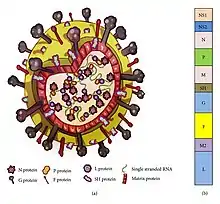

Genome

RSV has a negative-sense, single-stranded RNA genome.[2] The genome is linear and approximately 15,000 nucleotides in length.[3] It is non-segmented which means that, unlike influenza, RSV cannot participate in the type of genetic reassortment and antigenic shifts responsible for large pandemics.[4] It has 10 genes encoding for 11 proteins.[2][4] The gene order is NS1-NS2-N-P-M-SH-G-F-M2-L, with the NS1 and NS2 gene serving as nonstructural promoter genes.[29]

RSV is a medium-sized (~150 nm) enveloped virus. While many particles are spherical, filamentous species have also been identified.[2][3] The genome rests within a helical nucleocapsid and is surrounded by matrix protein and an envelope containing viral glycoproteins.[30] There are 11 proteins, described further in the table below.

| Location in the Virion | Protein | Alternative Name | Function | Additional Information |

|---|---|---|---|---|

| Lipid envelope (transmembrane surface proteins) | G | Glycoprotein | Viral attachment to ciliated cells of the host airway | F and G glycoproteins are the two major surface proteins that control viral attachment and the initial stages of infection. F and G proteins are also the primary targets for neutralizing antibodies during natural infection. |

| F | Fusion protein | Fusion of viral and host cell membranes; syncytium formation | ||

| SH | Small hydrophobic protein | Viroporin; ion channel | Participates in cell fusion, but no known neutralizing epitope | |

| Inner envelope face | M | Matrix protein | Assembly | |

| Ribonucleocapsid | N | Nuceloprotein | RNA-binding | Involved in genome transcription, RNA replication, and particle budding |

| P | Phosphoprotein | Phosphorylation | ||

| L | "Large" protein | RNA-dependent RNA polymerase | ||

| M2-1 | - | Transcription processivity factor | ||

| Regulatory | M2-2 | - | Regulation of transcription / RNA replication | |

| Nonstructural | NS-1 | - | Involved in evasion of the innate immune system | Act by inhibiting apoptosis and inhibiting Type I IFN signaling |

| NS-2 | - |